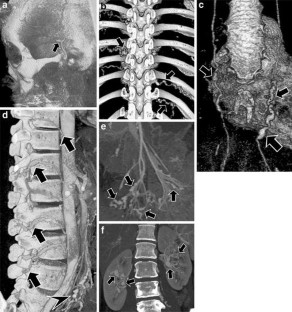

Polyarteritis nodosa: MDCT as a “One-Stop Shop” Modality for Whole-Body Arterial Evaluation

Polyarteritis nodosa is a rare disease, which is characterized by aneurysm formation and occlusion in the arteries of multiple systems. Due to its extensive involvement, whole-body evaluation is necessary for diagnosis and treatment monitoring. We report a case of polyarteritis nodosa using multidetector-row computed tomography (MDCT) as a “one-stop shop” modality for whole-body arterial evaluation. With precise protocol design, MDCT can be used as a reliable noninvasive modality providing comprehensive whole-body arterial evaluation.

Fig. 1